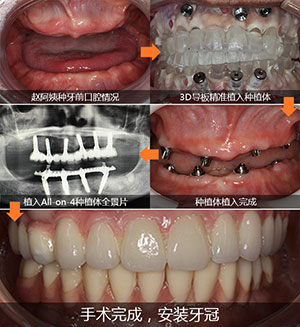

缺牙患者: 赵阿姨 缺牙情况: 全口牙缺失十多年,牙槽骨骨量差 主诊医生: 赵海涛院长 治疗方法: All-on-4全口种植牙技术 赵阿姨全口牙缺失,佩戴活动假牙十多年,饱受活动假牙困

缺牙情况:全口牙缺失十多年,牙槽骨骨量差

治疗方法:All-on-4全口种植牙技术

赵海涛院长从检查初,到最后手术,全程使用数字化导航导板种植系统,术前精准模拟种植的每个过程,打印3D导板,按照导板预先的轨迹植入种植体,戴临时牙冠,手术持续了两个半小时,术后赵阿姨就能啃苹果了。

赵海涛院长为赵阿姨在种好的植体上安装调试牙冠